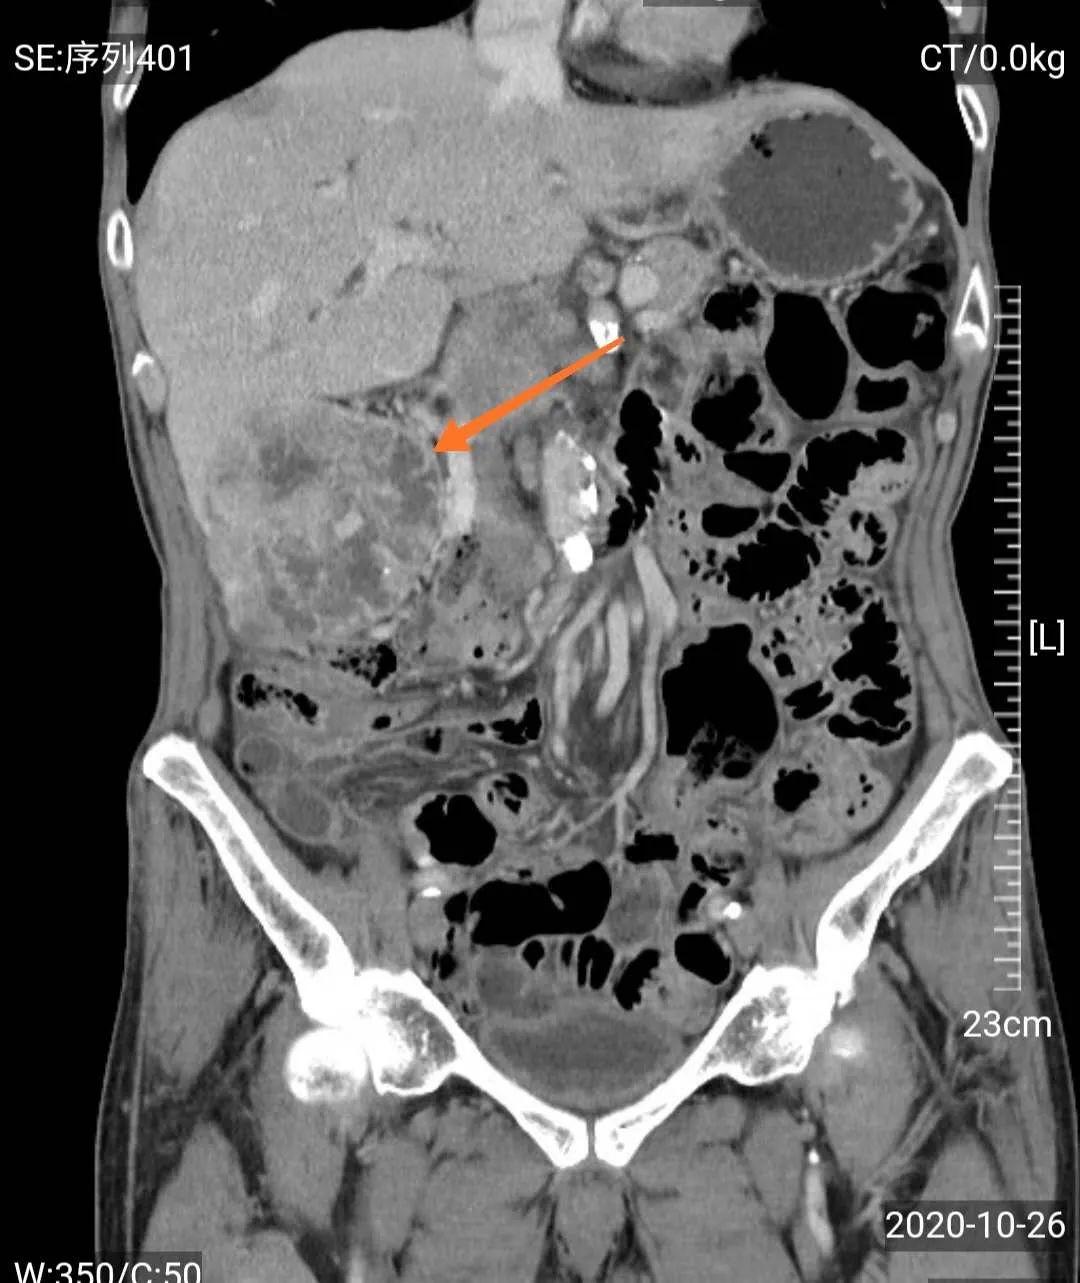

然而,门诊泌尿系超声检查发现,梁爷爷除了前列腺增生外,还有一个可怕的问题——右肾巨大肿瘤,考虑右肾癌可能性大。

经MDT团队研究,影像学团队分析认为老人诊断右肾癌相对明确,手术治疗是首选方案;心血管及肺病科团队认为老人虽然年龄大,高血压病史,但血压控制较好,心肺功能评估认为手术风险属于轻度;肿瘤科认为患者手术指征很明确,目前一般情况好,预期寿命长,内科治疗效果不及外科手术;中医治疗可以在外科手术后辅助,不能仅靠中医治疗。泌尿外科团队认为患者诊断考虑右肾癌,且左肾功能正常,右肾肿瘤巨大,建议根治性手术切除,考虑老人年纪大,开放手术创伤大,出血多,建议采用3D腹腔镜微创治疗。

手术前准备充分,我院泌尿外科主任徐战平主任医师主刀手术,手术过程非常顺利。梁爷爷术后恢复非常好,继续中医药调理,目前已能正常饮食和自理,痊愈出院。